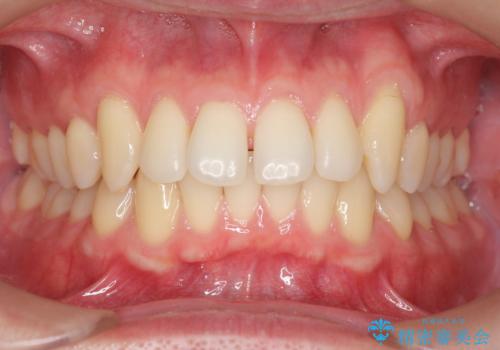

矯正治療か、セラミックで最短で治すかの選択肢を提示し、セラミックで治すことにしました。

利点は、早く終わる上に、保定の必要がないため負担が少ないことが挙げられます。

全て神経は取らずに、削りました。

長年コンプレックスだったすき間が閉じたとのことで、喜んでいただきました。